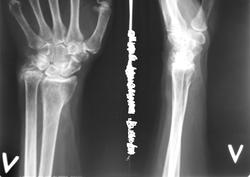

Случай №1 Пожилая женщина около года назад упала на руку. Пришла по поводу боли в ЛЗС.

А по первому случаю: у пациентки был перелом шиловидного отростка локтевой кости и лучевой кости в типичном месте. Теперь головка лучевой кости "просела" и лучезапястный сустав деформировался, отсюда и вторичные изменения в головке локтевой кости. Т.е. мы имеем посттравматический артроз л/з сустава.

Думаю, вопрос о корригирующей остеотомии здесь не стоит, так что - консервативное лечение.

Ну в первом-то случае понятен характер болей... Он связан с потерей конгруэнтности суставных поверхностей, то бишь посттравматическим деформирующим остеоартрозом. Тут тактика зависит от возможностей врача и пациента... Как думаете лечить?

В 1 случае - сказка про репку: локтевая давит на трехгранную, трехгранная - на крючковидную. Лучевая девиация кисти за счет проседания луча. Оссификация мягких тканей у шила локтевой. Ступенька между 1 и 2 рядами костей запястья по типу перилунарного...